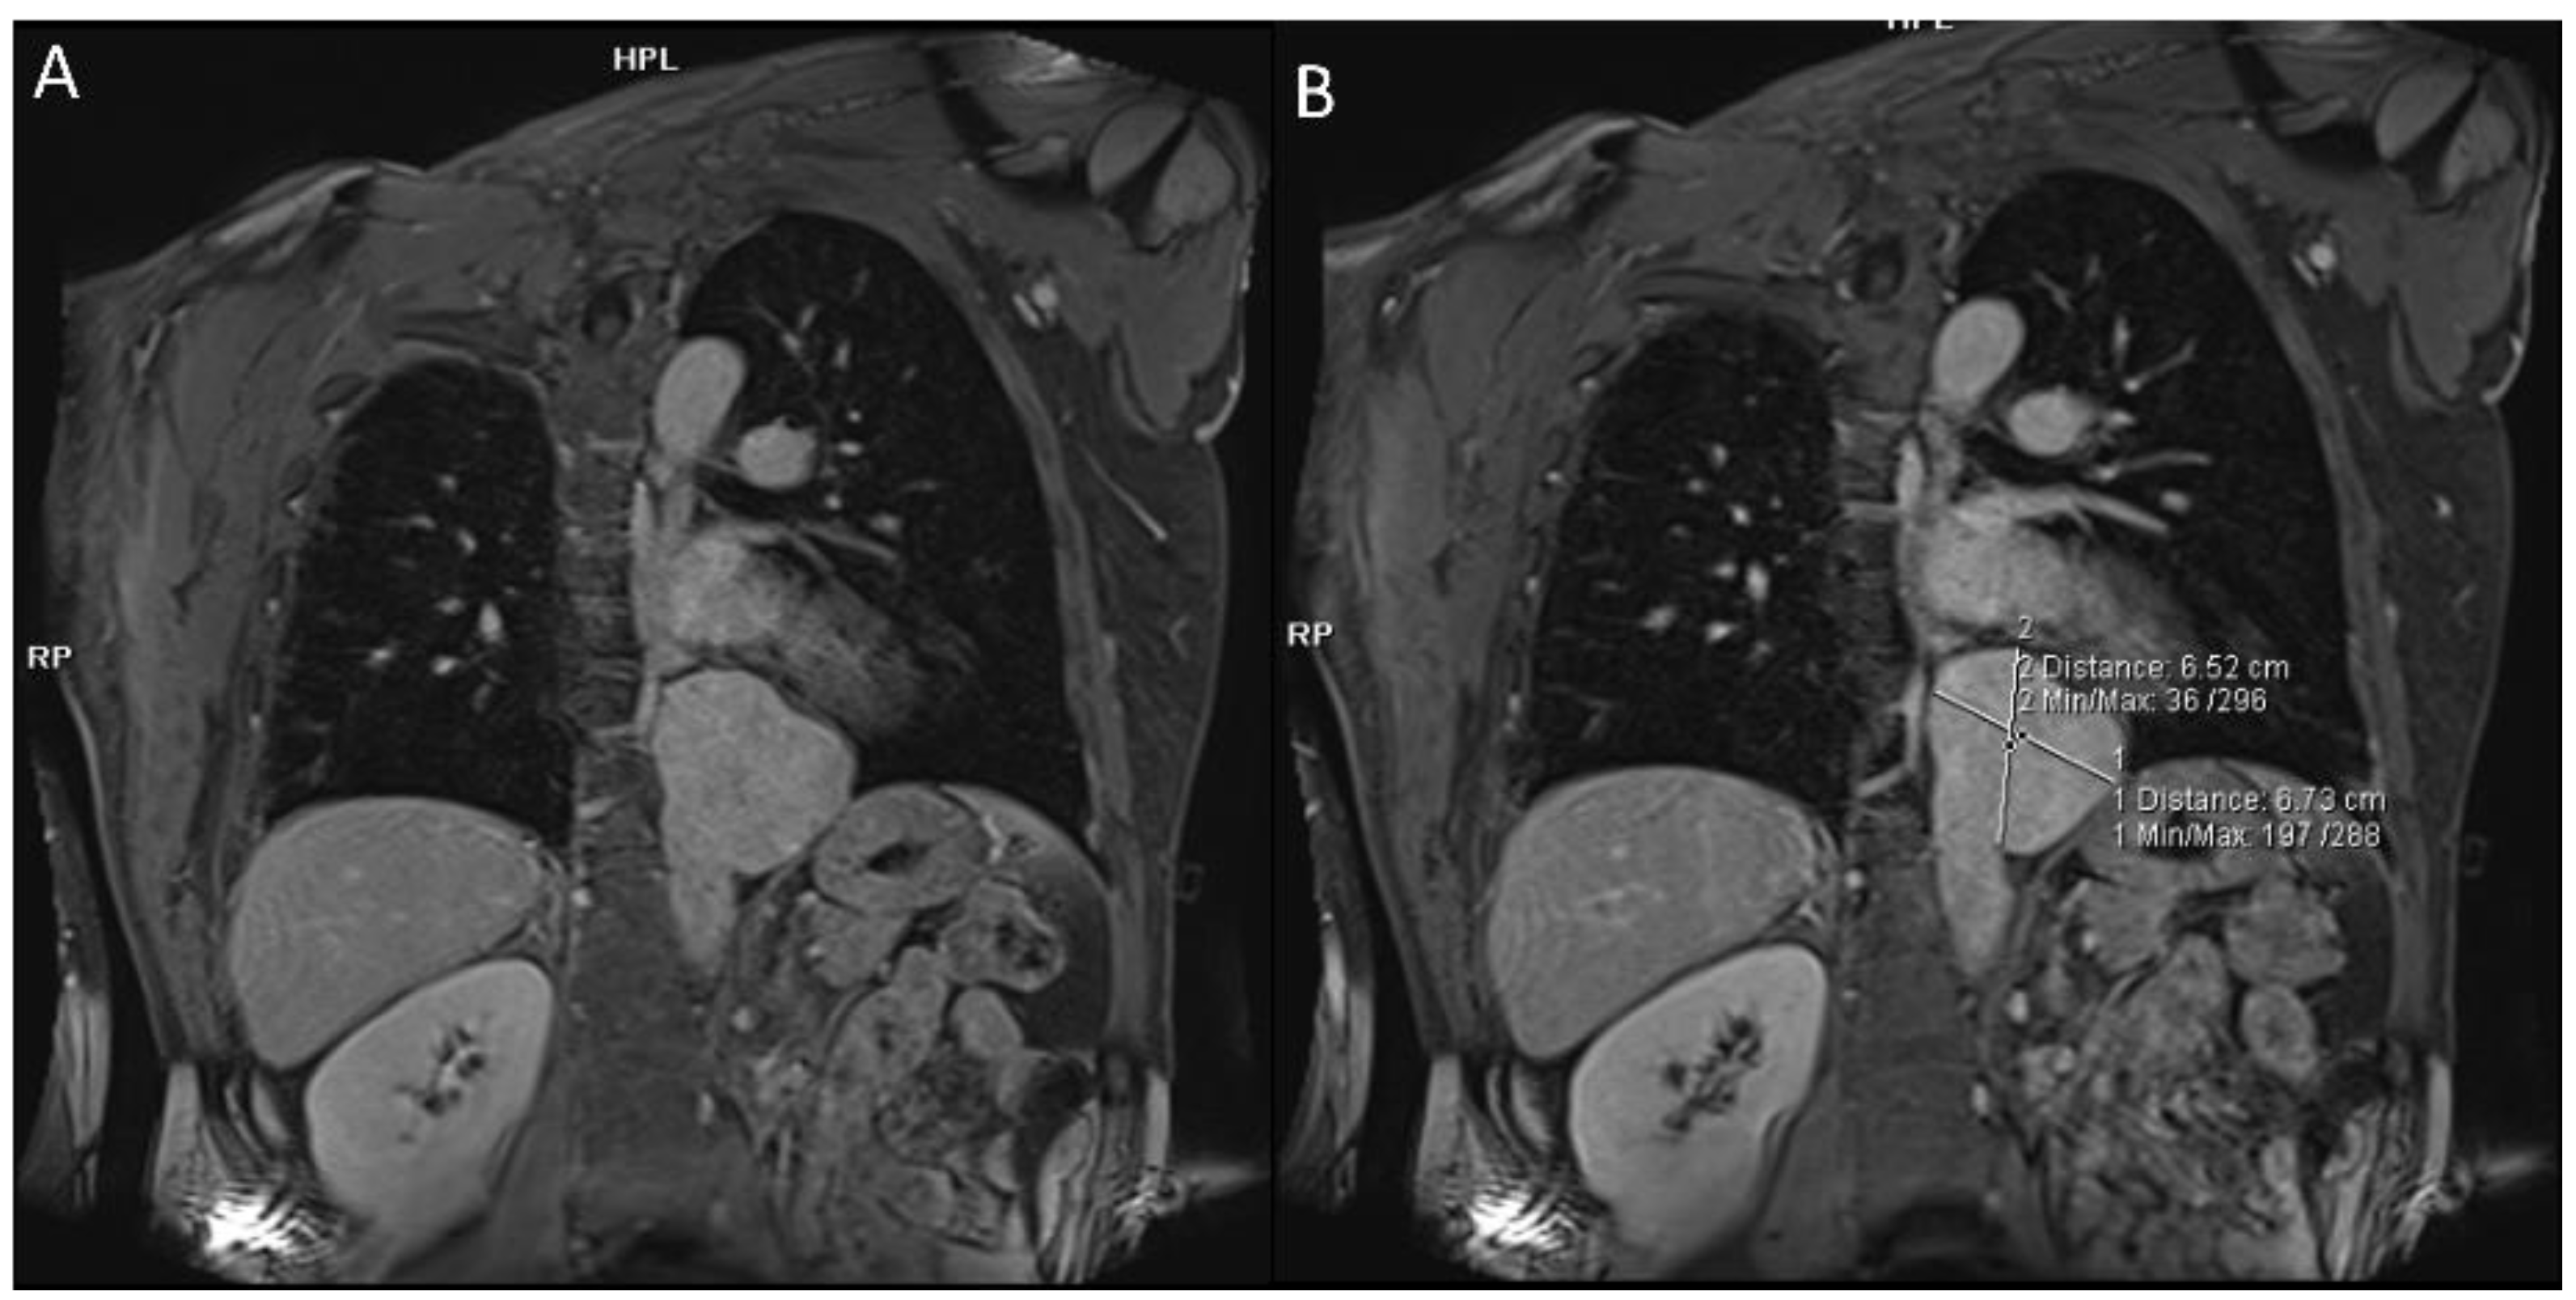

2.1.2. Pulmonary Arterial Manifestations

- Akpolat, T.; Danaci, M.; Belet, Ü.; Erkan, M.L.; Akar, H. MR Imaging and MR Angiography in Vascular Behçet’s Disease. Magn. Reson. Imaging 2000, 18, 1089–1096. [Google Scholar] [CrossRef]